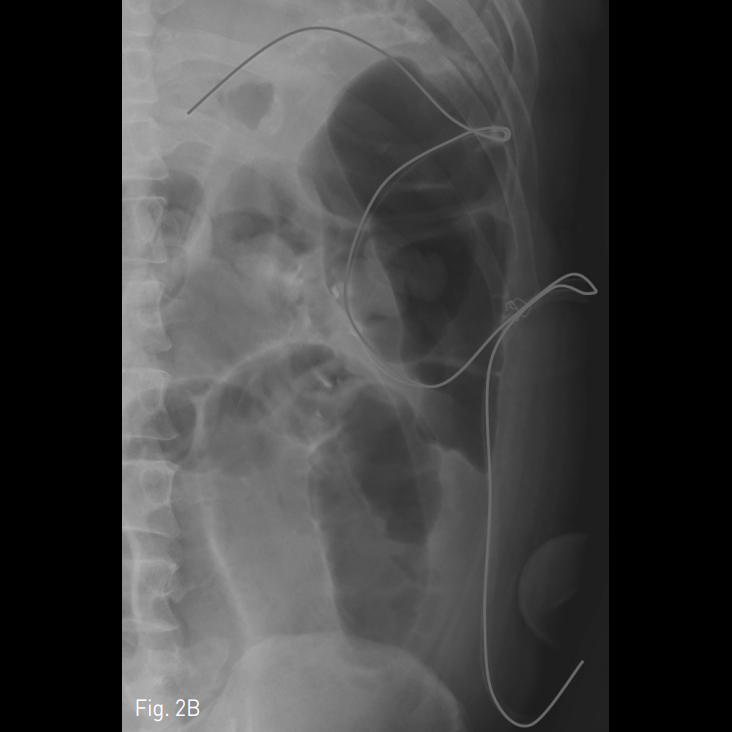

해당 부위 주변으로 Jackson-Pratt관이 거치되어 있으나 효과적인 배액이 안되고 있는 것을 알 수 있으며 복부단순촬영에서 해당 관은 복강 내에서 매우 구불구불한 형태로 보이고 있으며 중간 부위에서는 U자 모양의 회전 부위도 보이고 있어 단순히 유도철사를 이용한 카테터 교환은 어려울 것으로 생각되었음 (Fig. 2).

Fig. 2

A-B. An erect abdominal plain radiograph shows Jackson-Pratt drainage catheter with tortuous passageway including U-turn course (annotated with blue colored line).